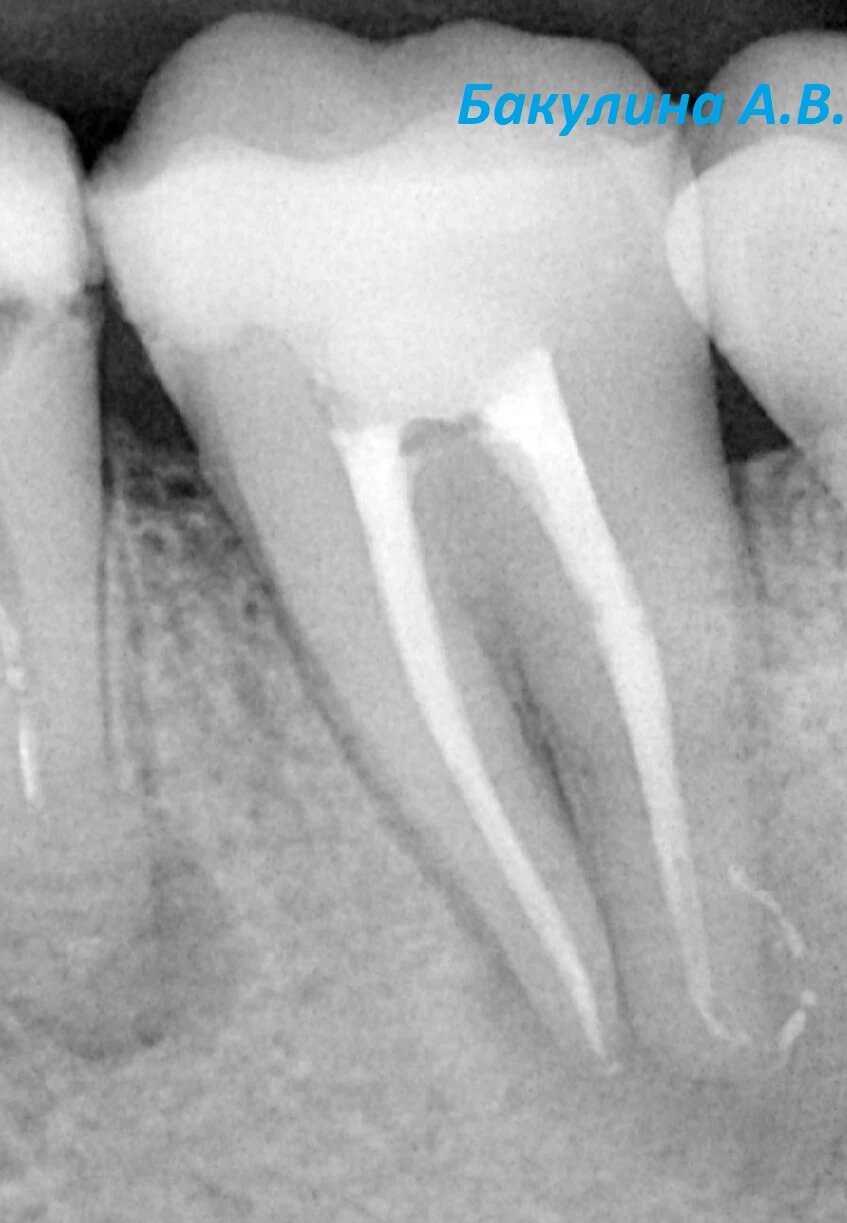

Лечение корневых каналов зуба 3.7. Стрелкой на первом фото указан размер очага воспаления костной ткани. Второй снимок-контроль пломбирования каналов. Третий снимок- активное заживление очага (компьютерная томография через 5 месяцев).